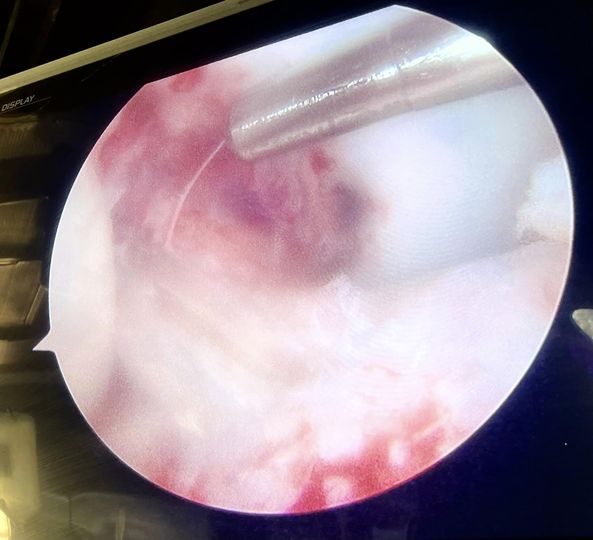

18 year old footballer with torn Acl, remnants of which is still attached to both sides of bone, in such cases, preserving the remaining stumps of Acl that carries nerves and proprioception (joint position sensation) and managing our reconstruction around that may well be an added boon for someone who is aspiring to be a professional footballer.arthroscopy